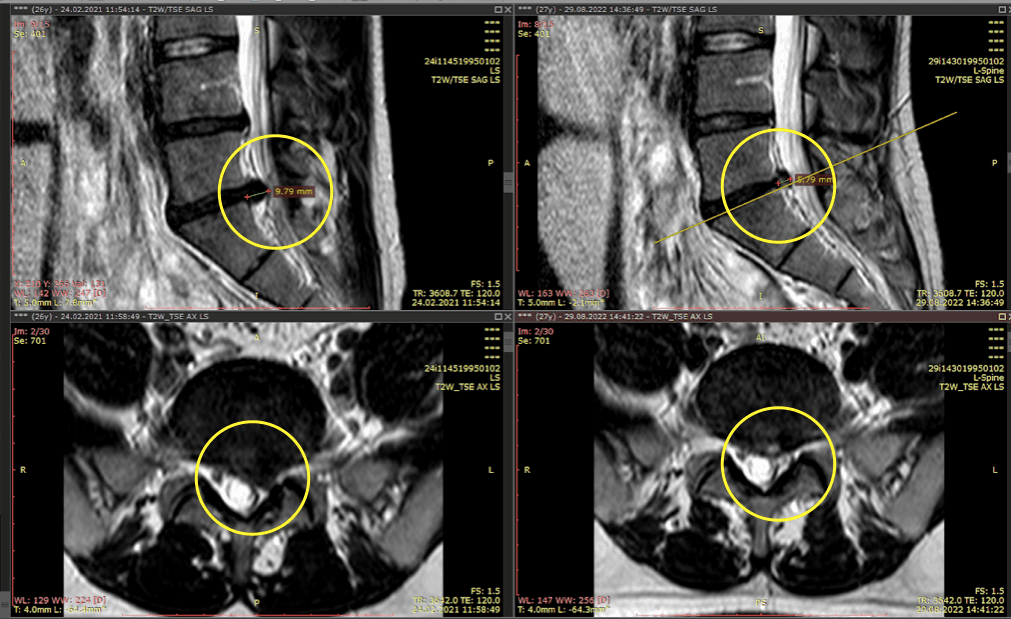

Ти приходиш до лікаря, а він такий: «Давай подивимось, що буде, якщо я натисну тут». І натискає. І одразу розумієш, що жартів не буде. Однак є ще й МРТ або рентген — на випадок, якщо раптом ти ще не переконався, що твої враження не вигадка.